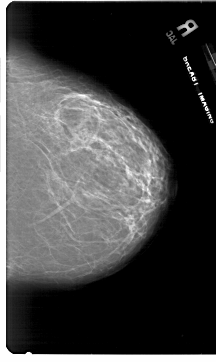

A_1787_1.RIGHT_MLO

RIGHT_MLO LINES 6871 PIXELS_PER_LINE 4261 BITS_PER_PIXEL 12 RESOLUTION 43.5 NON_OVERLAY